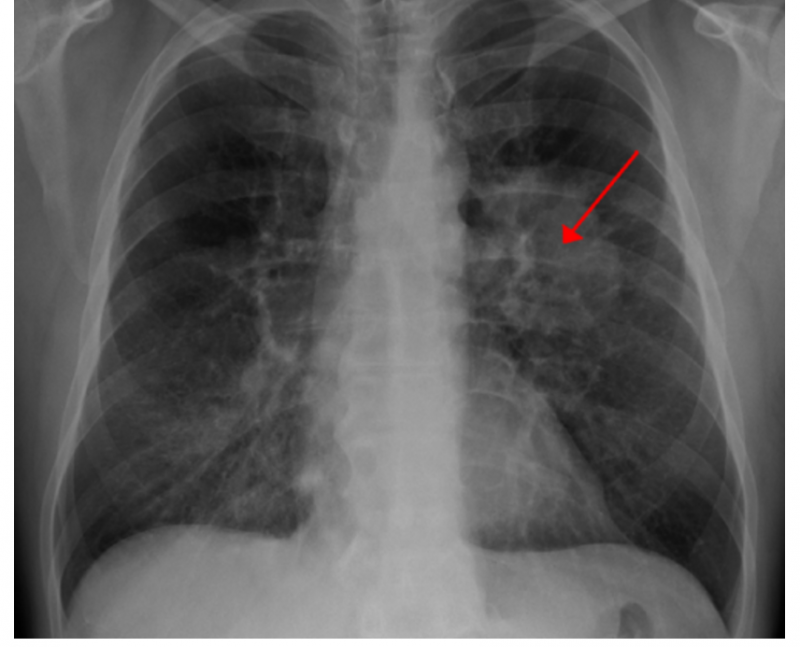

对于吸烟者和戒烟者来说,肺癌的威胁总是隐藏在阴影中。为了避免整日忧心忡忡,可以通过肺部CT扫描及时发现肺癌,并尽早阻止它尽早;或者是虚惊一场,没有任何癌症迹象。

现在,一项新的研究显示如何为每位患者个性化肺癌筛查决策。这些结果可以帮助医生调整对患者的建议,以便患者了解个人肺癌风险以及筛查的潜在益处和危害,但是这基于患者对寻找问题和处理问题的态度。Tanner Caverly,M.D.,M.P.H.领导的团队使用了来自主要肺癌筛查研究的数据和根据现行指南筛选潜在筛查人群的国家数据,进行了基于计算机的新模拟分析。